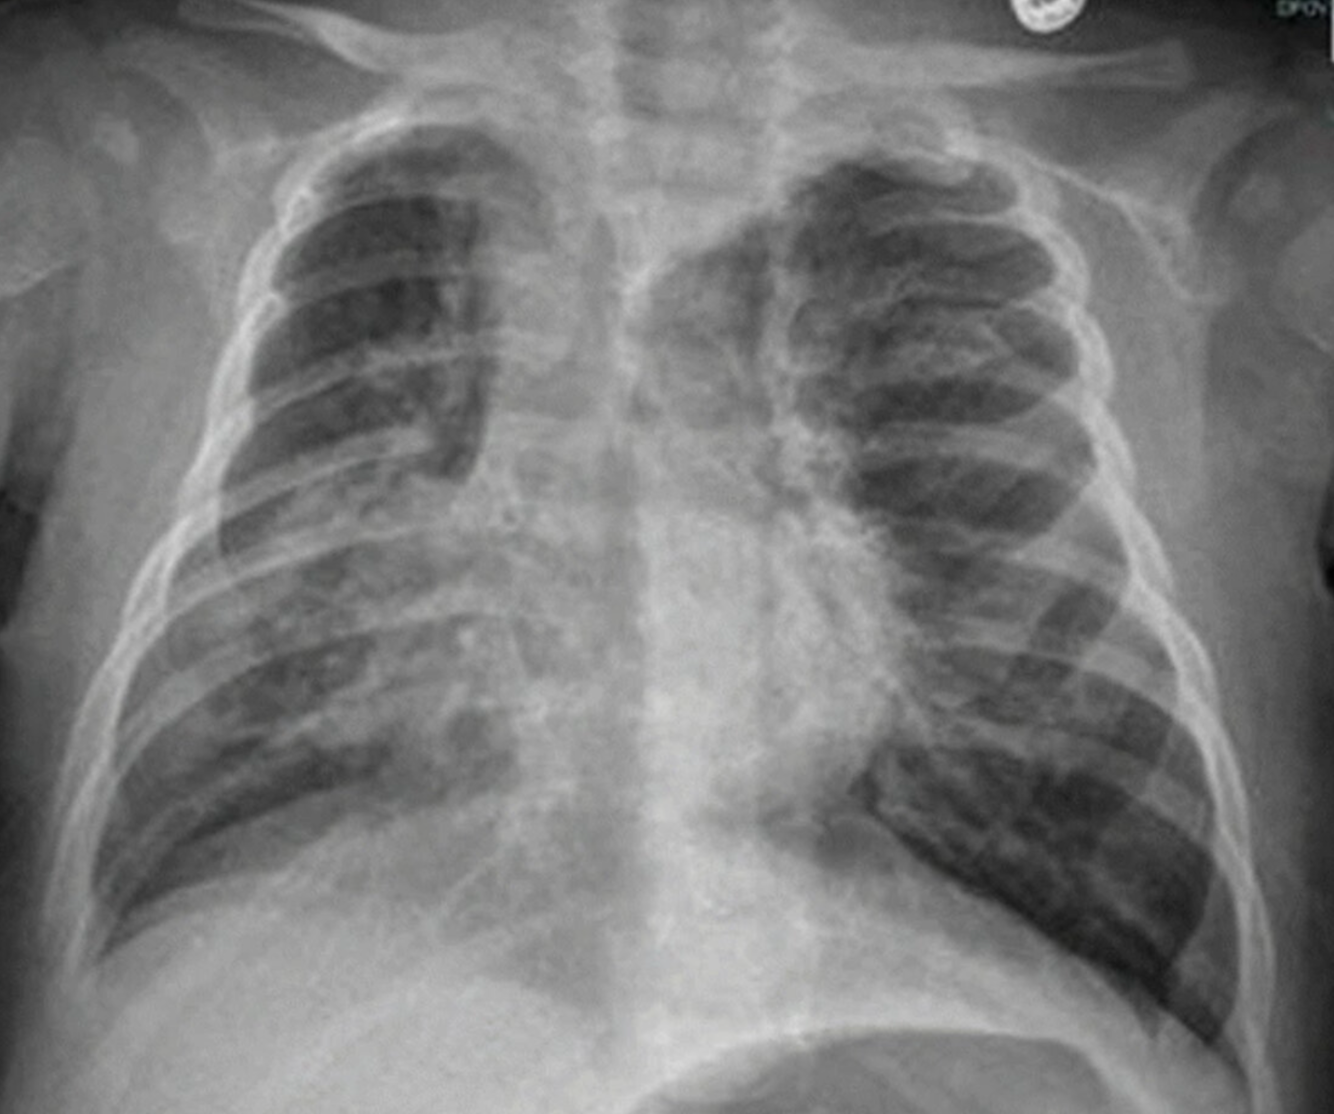

Bilateral hyperinflation and right lung consolidation

X-ray chest (AP view) of a child with viral bronchiolitis and focal pneumonia

Bilateral perihilar peribronchial thickening (examples of bronchi indicated by green lines) is accompanied by hyperinflation with diaphragmatic depression (indicated by white lines and arrow). In the right lung, a superimposed area of consolidation from pneumonia (red overlay) is associated with atelectasis and ipsilateral mediastinal shift (indicated by black arrow).

Black outline: trachea; white dashed line: physiological position of left hemidiaphragm